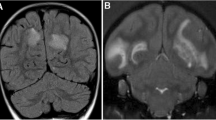

The MRI scans revealed in all six cases the presence of lesions in the white matter, albeit different in size and number, while in two cases (M08093 and M09083), we found lesions also in the grey matter. In monkey M08093, the highest white matter lesion volume was detected. Figure 2 shows the presence of lesions in a selected coronal slice from each marmoset brain. The T2-weighted images (T2W) reveal lesion-like abnormalities detected in the white matter, while the corresponding WAIR images of the same slice show a grey matter lesion. Overall, the MRI-detectable brain lesion load in this new model was remarkably low compared to the model induced with rhMOG/CFA, despite the presence of similar serious neurological defects in both models.

MRI images. MRI scans were made of formalin fixed brains. A representative slide of T2-weighted (T2W) and white matter attenuated inversion recovery (WAIR) images are depicted. In addition, a 3D reconstruction was made of all T2W images. The left two columns display typical slices through the brains on which lesions in the white (red arrowheads) and grey (blue arrowheads) matter lesions can be discerned. The 3D volume shows the total outlined volume of white (red) and grey matter (blue) lesions for each animal. Note that grey matter lesions were only observed in M08093 and M09083